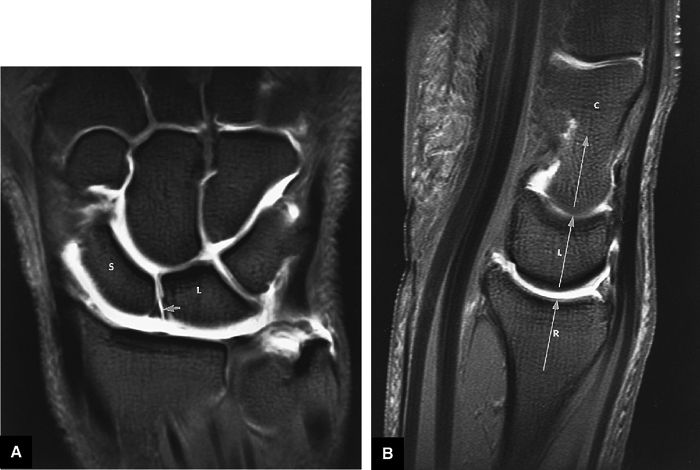

FIGURE 10.89 ● (A) DISI with dorsal tilting of the lunate (curved arrow) without volar shift. Note the dorsal displacement of the capitate relative to the radius. The capitolunate angle (double-headed arrow) measures 32°. (B) Palmar tilting of the scaphoid (curved arrow) causes an abnormally increased scapholunate angle (double-headed arrow) of 124°. D, dorsal; V, volar.

FIGURE 10.90 ● Scapholunate ligament tear with DISI. (A) Traumatic avulsion of the lunate aspect of the scapholunate ligament on a fast STIR coronal image. The scapholunate interval is widened with direct extension of fluid filling the tear site (large straight arrow). Ligament fibers are still attached to the radial aspect of the lunate (small straight arrow). Morphology is amorphous at the avulsed scaphoid remnant (curved arrow). (B) The capitolunate angle (arrow) is increased to 46°, and there is associated dorsal tilting of the lunate. (C) The scaphoid tilts palmarly with an increased scapholunate angle (arrow) of 142°.